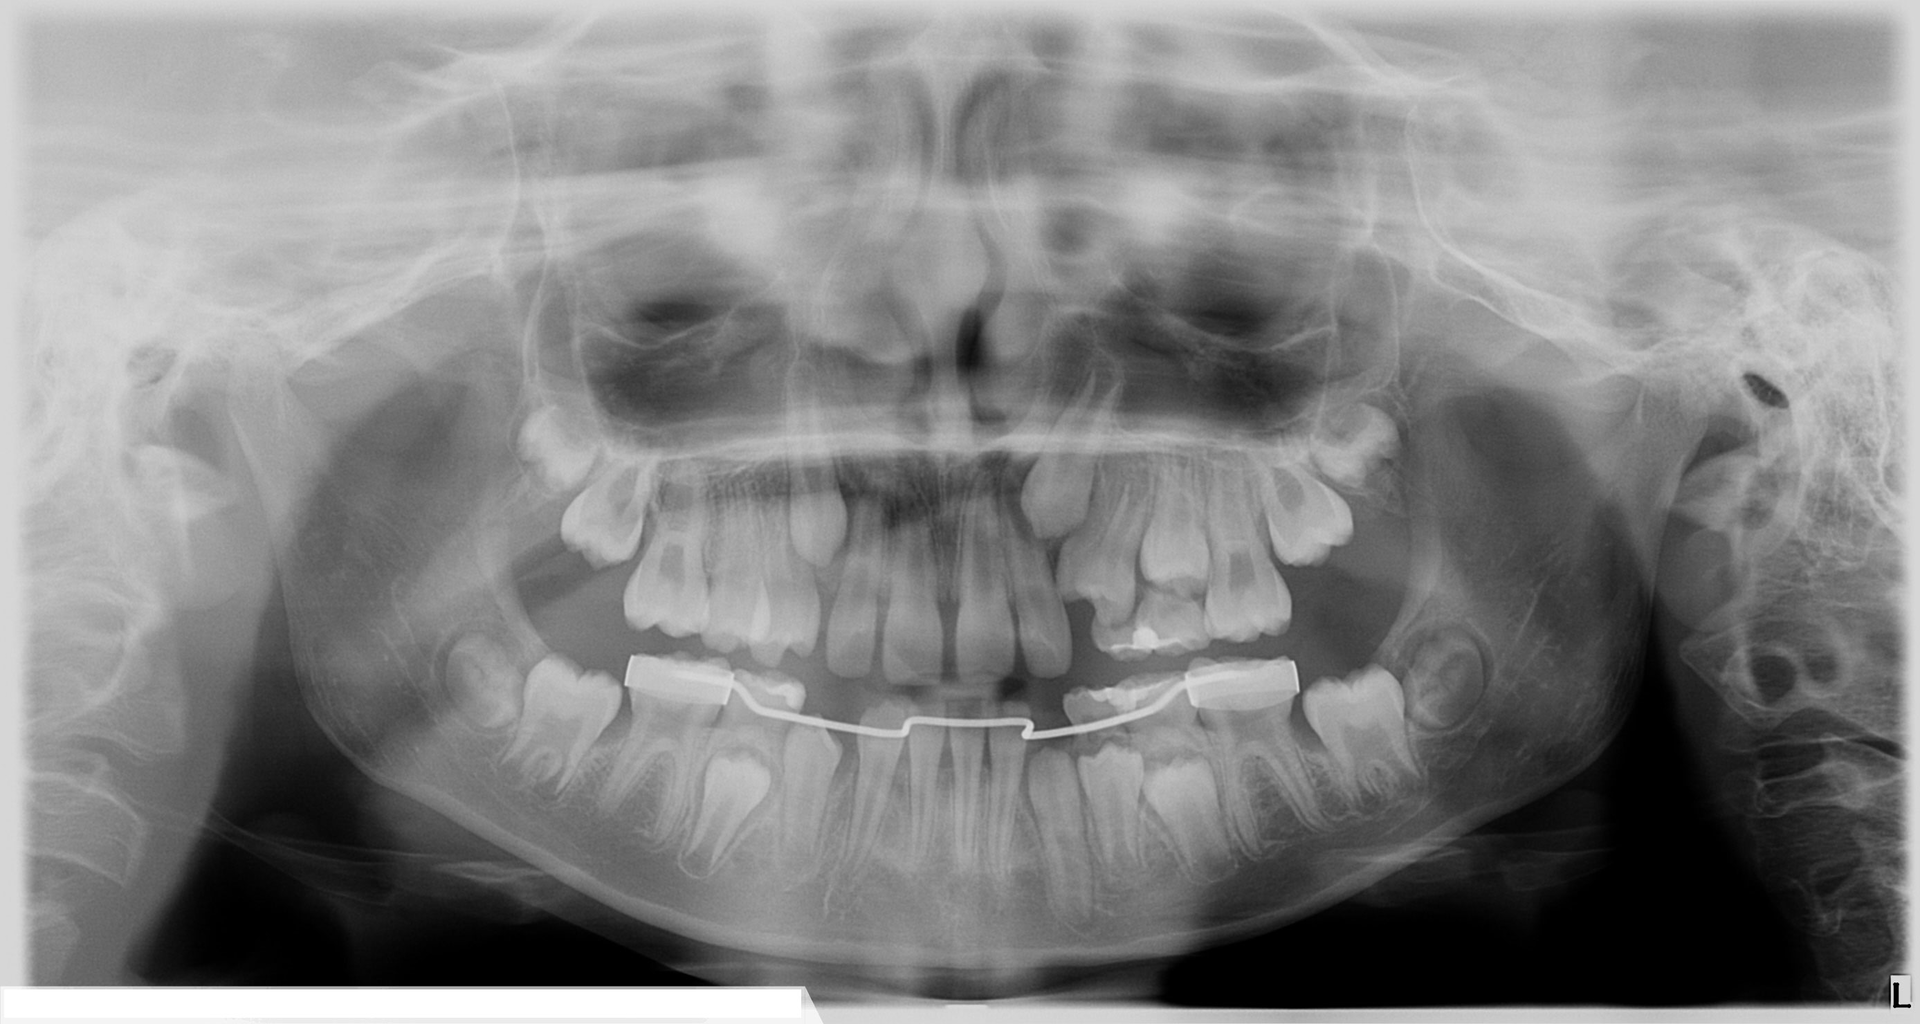

While impactions can cause resorption on adjacent teeth, 2D imaging can’t always provide the clarity needed to elucidate the proper path forward. Read the case study below to ...